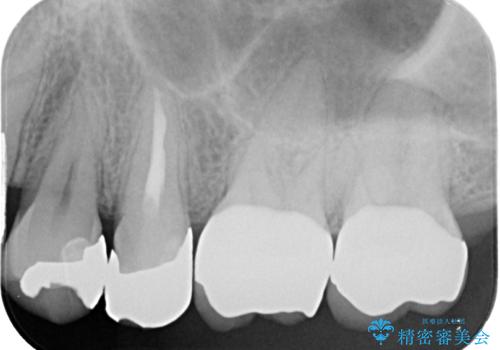

歯と歯茎の間に圧排糸と言われる糸を入れてシリコーン印象材にて型どりをしました。

見た目、機能面共に満足していただけました。

今後もメンテナンスで通ってもらいながら、治療が必要になってきたところは順次行っていく予定です。